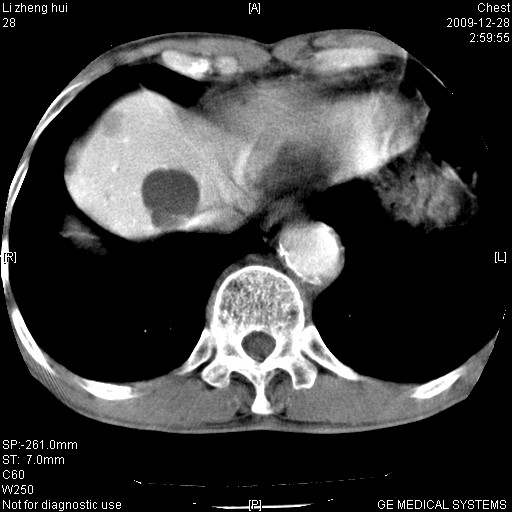

标题: CT23859:胸主动脉瘤

男  79岁 胸部痛急诊入院,晚上做的增强

考虑主动脉瘤?(增粗、钙化、壁血栓?)

支持,另有肝囊肿。

1)考虑胸主动脉壁间血肿或夹层动脉瘤。2)多发性肝囊肿。

1)考虑胸主动脉附壁血栓或夹层动脉瘤。2)多发性肝囊肿。